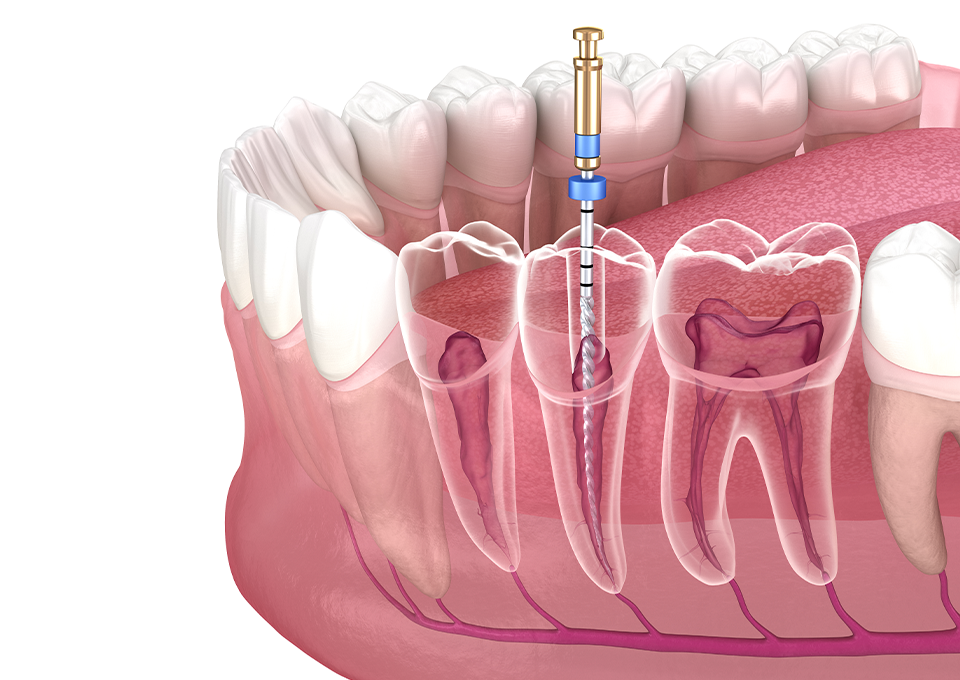

根管治療

- 歯がズキズキと痛む

- できるなら歯を残したい

- 歯の中に膿が溜まっている

根管治療は、歯の根っこの中にある管の治療です。むし歯が進行すると、歯の根っこにまで感染が広がって、とても強い痛みが出ます。

根管治療では感染した神経を取り除き、管の中を殺菌・消毒して薬を詰めて密閉することで、無菌状態に近づけます。

以前は、抜歯以外の選択肢がありませんでしたが、根管治療によって歯を残す可能性が広がりました。